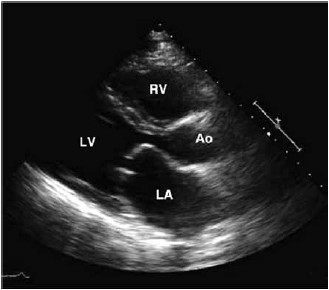

Considerando a anormalidade valvar demonstrada a seguir, é correto afirmar

(Arquivo pessoal: imagem usada com autorização.)